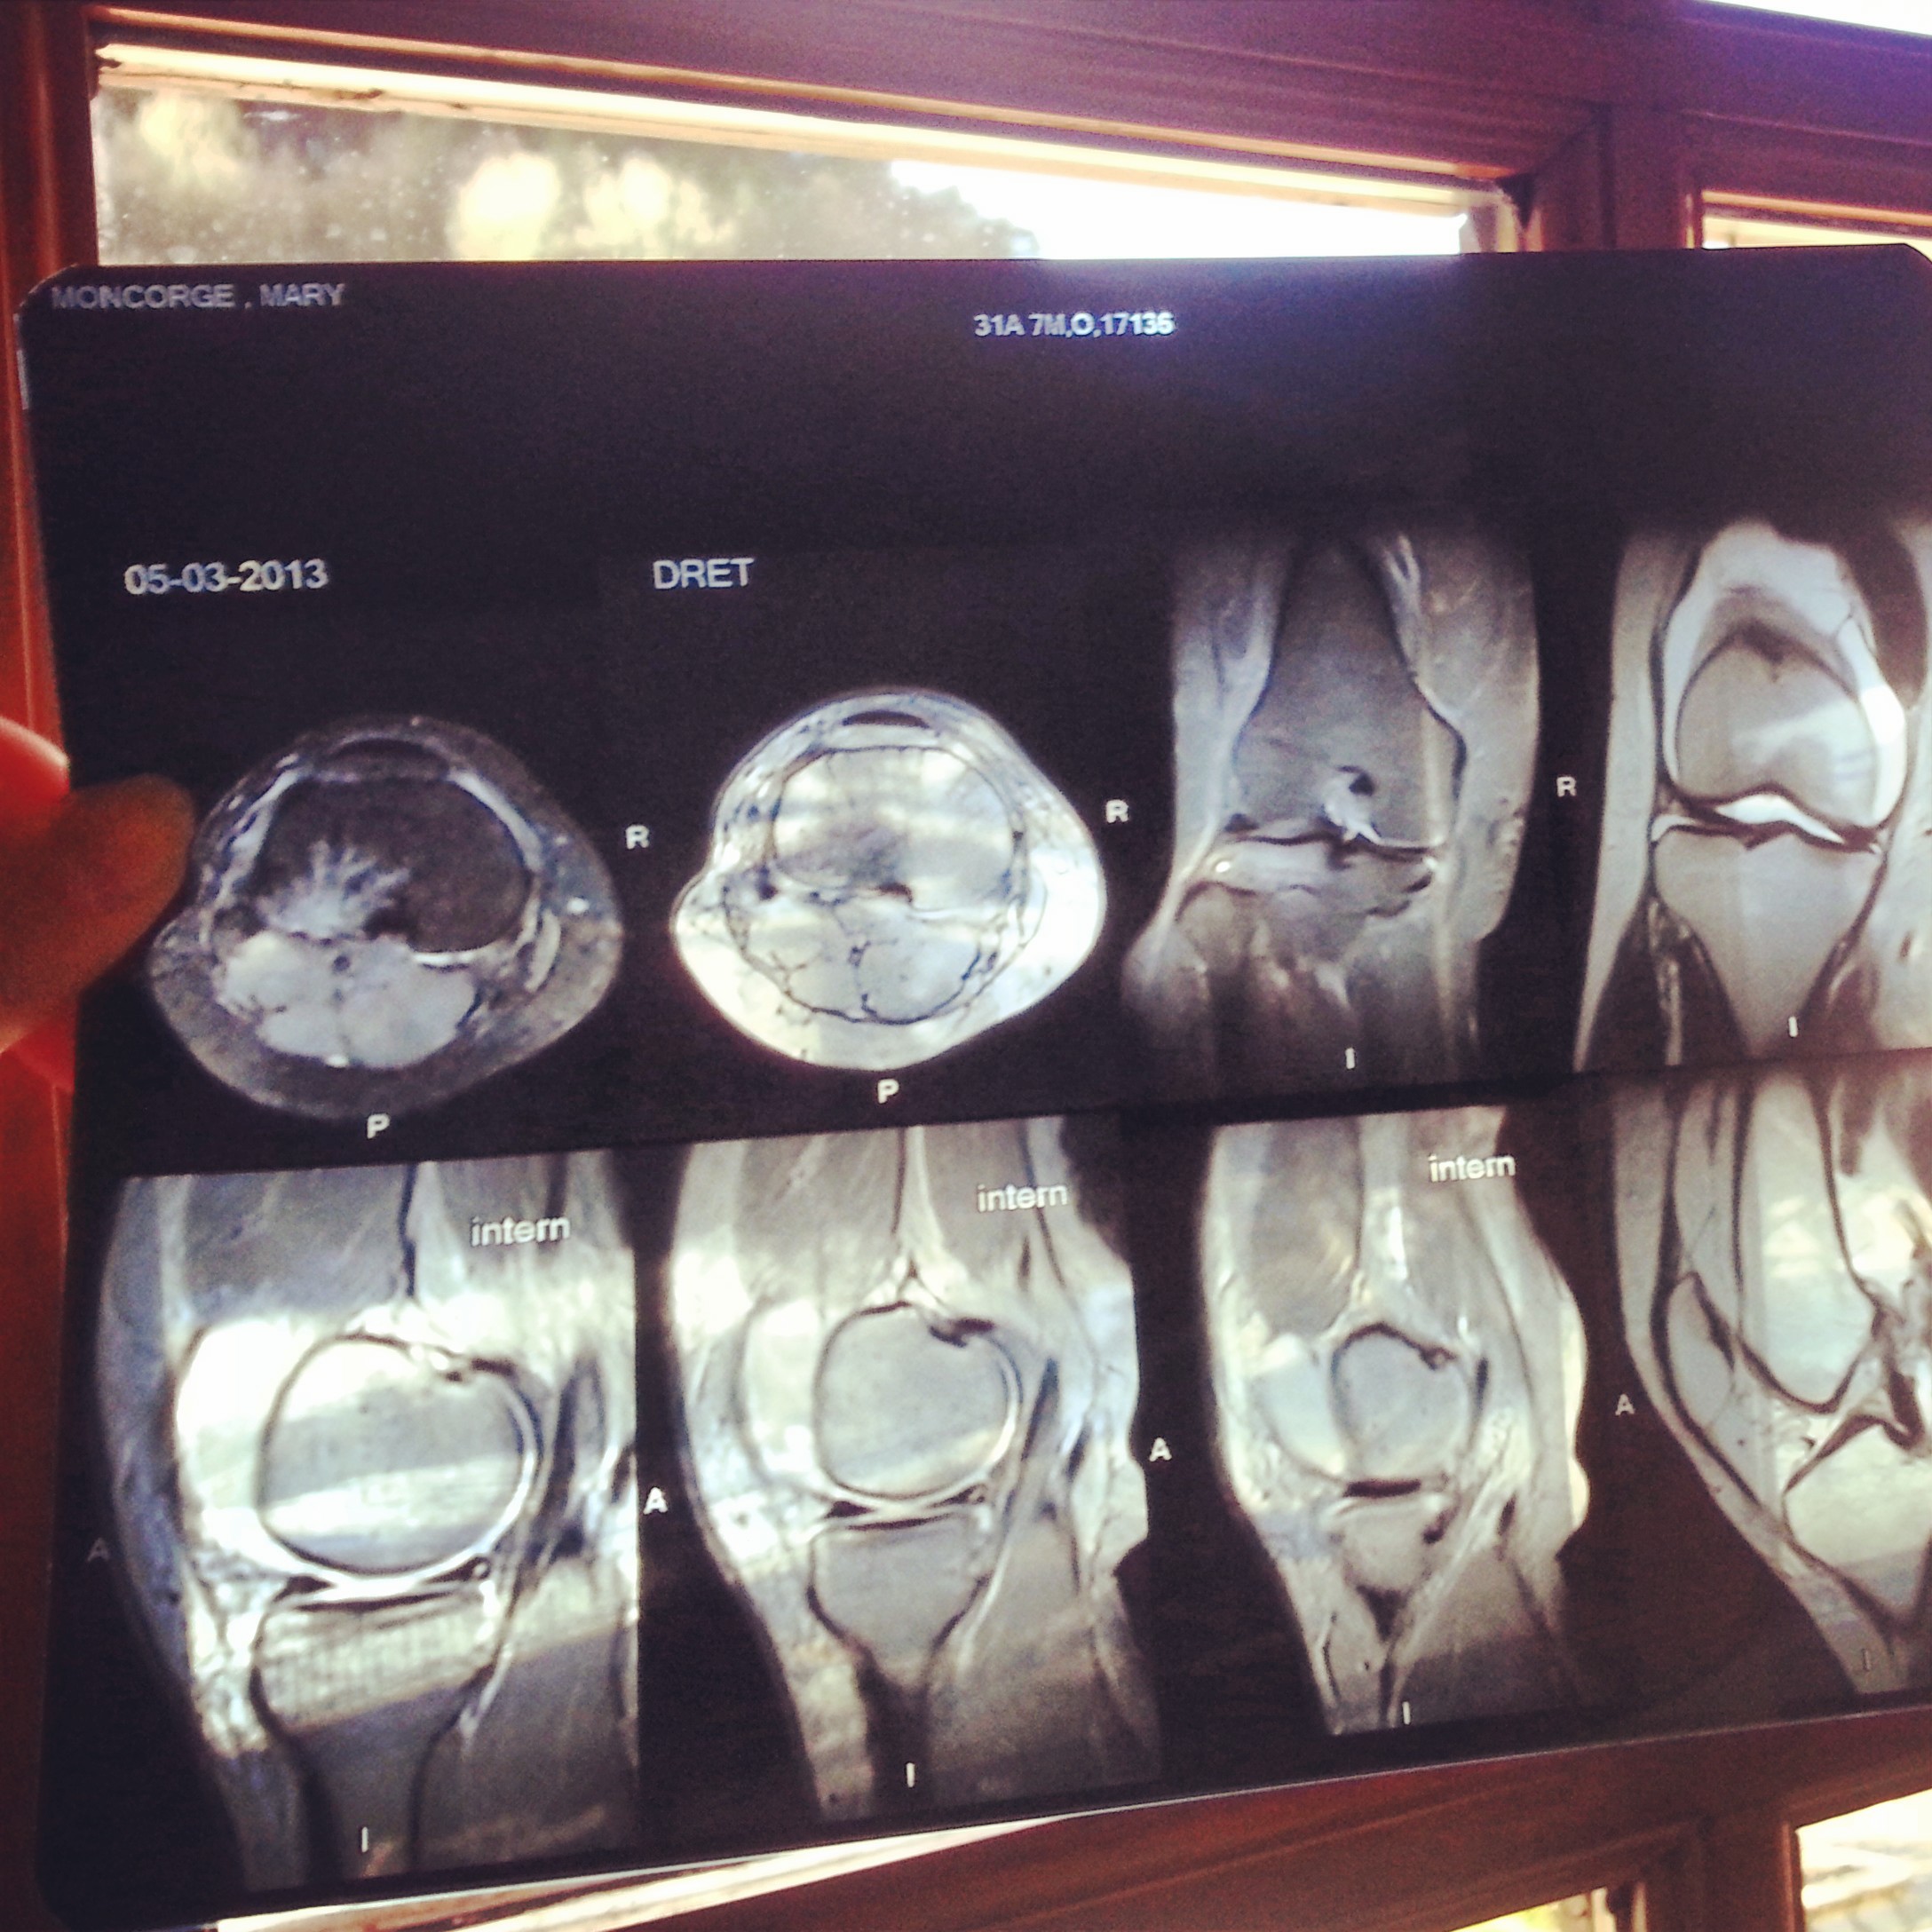

The following week, I went to Punta Ala, Italy to check out the possible courses of the fist Enduro World Series and did so on a bad knee, which lead to fully destroying it: fully ruptured ACL, partially ruptured meniscus, fractured tibia. I definitively did a grand slam on my poor knee.

After meeting with the orthopedic surgeon (also, I’ve to admit that before I did the MRI, I went on racing and winning the Mondraker Enduro Series #1 in Las Gavarres near Girona, on my jacked up knee), I decided to opt for an external graft to fix my knee as efficiently as possible but also without damaging another part of my body by using a tendon or ligament to replace my annihilated ACL for faster recovery.